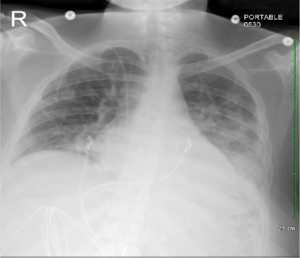

A 30-year-old African American female patient presented to the emergency room with complaints of dyspnea and high-grade fever for three days. The patient denied sore throat, chest pain, abdominal pain, and diarrhea. Past medical history was significant for multiple sclerosis, well controlled with ocrelizumab with no episodes of remission. The patient had up-to-date immunization status along with the COVID-19 vaccine. On admission vitals, signs showed blood pressure 113/56 mmHg, heart rate 113 beats per minute, respiratory rate 28 breaths per minute, and spO2 95% on room air. The physical examination revealed bilateral crackles on chest auscultation, and other systemic examinations were unremarkable. Initial laboratory workup showed an elevated white blood cell count (WBC) of 18.5 × 103/mcL and a normal platelet count of 264 × 103/mcL in the emergency department. Chest x-ray showed bilateral multifocal consolidations. The patient tested negative for COVID-19 polymerase chain reaction (PCR) and for the rapid influenza antigen test. She was treated with broad-spectrum antibiotics for pneumonia. Blood cultures ½ showed growth of Haemophilus influenzae biotype 2. After 48 hours, we discontinued intravenous antibiotics and started the patient on oral antibiotics based on her down-trending WBC count and lack of supplemental oxygen requirement. During hospitalization, on day three, CBC showed a platelet count of 540 × 103/mcL, which we believe was due to sepsis response. On day six of hospitalization, the patient complained of chest pain, shortness of breath, sore throat, low-grade fever, and watery diarrhea.

Computed tomography angiography (CTA) chest to rule out pulmonary embolism was negative, and the chest x-ray showed new bilateral opacities (Figure 1). A complete blood count revealed a normal white blood cell count and an isolated jump in platelet count to 1209 × 103 /mcL from 264 × 103 /mcL (Figure 2). The patient tested positive for COVID-19 on a nasopharyngeal swab PCR test. The initial COVID-PCR test was negative, and we believe the patient had a hospital-acquired infection. We started supplemental oxygen, as the patient maintained SpO2 88% on room air, dexamethasone, and remdesivir, and consulted hematology/oncology for isolated extreme thrombocytosis. An extensive workup was conducted to rule out myeloproliferative disorder, including Janus kinase 2 (JAK2) mutation, BCR/ABL fusion, iron deficiency anemia, and acute phase reactants, including C-reactive protein, erythrocyte sedimentation rate, and interleukin6 and 8 (IL-6, IL-8). The patient was discharged after clinical improvement in symptoms, with outpatient follow-up for a myeloproliferative disorder workup, which turned out to be negative.